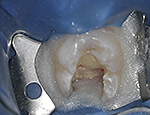

Fig 4. This maxillary first molar was to have endodontic therapy following diagnosis of irreversible pulpitis.

Figure 4

Fig. 6 A small access opening was prepared and canals explored.

Figure 6

Fig. 7 This conservative size preparation was enough to explore and find the three main canal orifices to the root canals.

Figure 7

Fig. 8 The MB2 canal, however, was not discovered until the preparation was widened to a rhomboidal shape, and the mesial dentinal shelf hiding the MB2 was removed with the aid of a bur and ultrasonic handpiece.

Figure 8